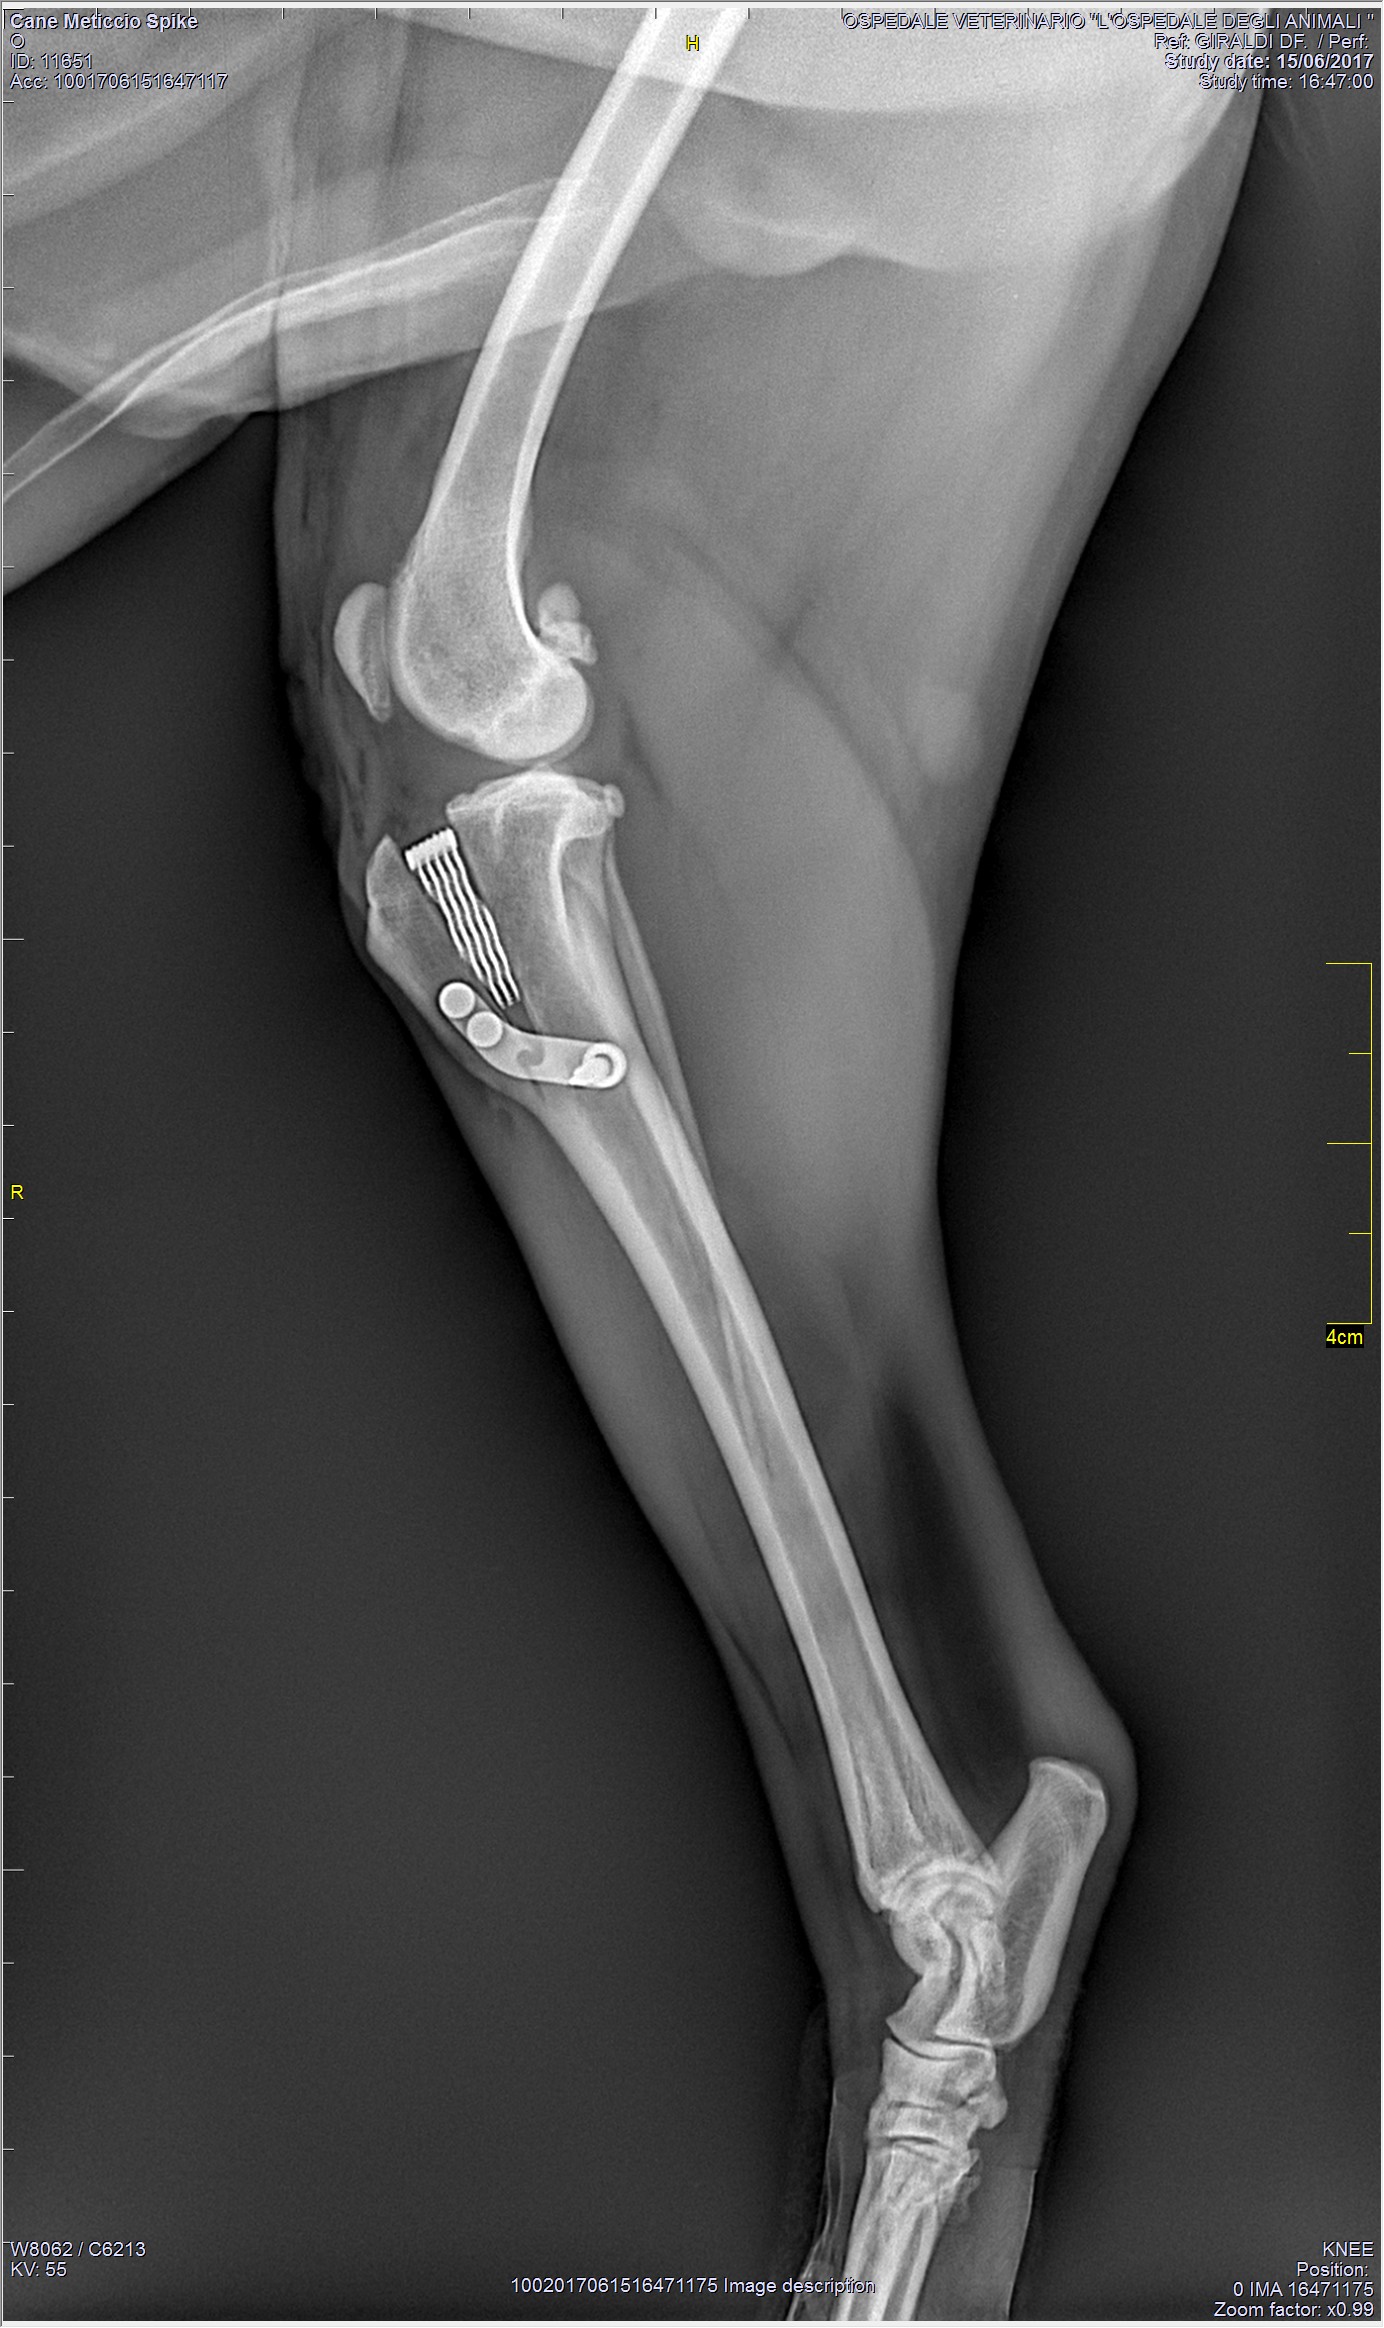

TPLO - Tibial Plateau Leveling Osteotomy

La tecnica TPLO (Osteotomia di livellamento del piatto tibiale) è attualmente una delle metodiche chirurgiche più utilizzate per il trattamento della rottura del legamento crociato craniale nel cane. Essa revede l’esecuzione di un'osteotomia radiale, eseguita con strumentario apposito, la rotazione caudale del segmento prossimale tibiale e la stabilizzazione dei monconi tibiali mediante placca.

Questa tecnica non prevede alcuna sostituzione del legamento crociato in quanto, mediante una modificazione della geometria articolare, permette di ottenere l'annullamento di forze indesiderate. In particolare, mediante la correzione dell’inclinazione del piatto tibiale, si propone di assicurare la stabilità dinamica cranio-caudale a carico dell’articolazione del ginocchio durante la fase d’appoggio del passo.

I vantaggi di questa tecnica chirurgica comprendono la precisione geometrica e il mantenimento nella posizione dell'articolazione del ginocchio, senza modificarne la biomeccanica.